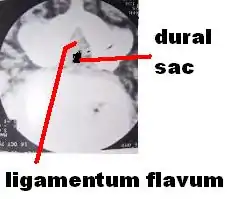

The term neurogenic claudication is sometimes used interchangeably with spinal stenosis. However, the former is a clinical term, while the latter more specifically describes the condition of spinal narrowing.[4] NC is a medical condition most commonly caused by damage and compression to the lower spinal nerve roots.[5] It is a neurological and orthopedic condition that affects the motor nervous system of the body, specifically, the lower back, legs, hips and glutes.[5][6] NC does not occur by itself, but rather, is associated with other underlying spinal or neurological conditions such as spinal stenosis or abnormalities and degenerative changes in the spine. The International Association for the Study of Pain defines neurogenic claudication as, "pain from intermittent compression and/or ischemia of a single or multiple nerve roots within an intervertebral foramen or the central spinal canal.[4] This definition reflects the current hypotheses for the pathophysiology of NC, which is thought to be related to the compression of lumbosacral nerve roots by surrounding structures, such as hypertrophied facet joints or ligamentum flavum, bone spurs, scar tissue, and bulging or herniated discs.[7]

Degenerative disc disease (DDD) may trigger the pathogenesis of neurogenic claudication. When intervertebral discs degenerate and change shape in DDD, the normal movements of the spine are interrupted. This results in spinal instability and more degenerative changes in spinal structures including facet joints, ligamentum flavum, and intervertebral discs. These pathologic changes result in narrowing of the vertebral canal and neurovascular compression at the lumbosacral nerve roots.[1][17] The compression of these spinal nerve roots that control sensation and movement in the lower body results in the tingling, pain and weakness NC patients often experience. However, because the severity of symptoms does not correlate well with the degree of stenosis and nerve root compression, a clear understanding of the specific pathogenesis remains challenging.[7]

These changes in blood flow may occur during back extension when shifts in vertebral structures and ligaments narrow the spinal canal and compress the neurovasculature.[15] Compared to a neutral position, extended spines exhibit 15% less cross-sectional area of the intervertebral foramina, and nerve root compression is present one-third of the time.[10] These dynamic changes in the shape of the spinal canal are more pronounced in individuals with spinal stenosis. The amount of narrowing may be 67% in LSS compared to 9% in healthy spines.[1]

Depending on the cause and severity of the condition, surgical options for NC vary. Symptoms of LSS, including NC, are the most common reason patients 65 and older undergo spinal surgery. Surgery is generally reserved for patients whose symptoms do not improve with nonsurgical treatments, and the main objective of surgery is to relieve pressure on the spinal nerve roots and recover normal mobility and quality of life.[10] Lower Spinal Decompression is considered the mainstay of surgical treatment.[2] In this procedure, the ligamentum flavum is first removed, followed by the removal of the superior facet osteophyte in the spinal canal, and then the decompression of the spinal nerve root.[5][11] Another surgical method of decompression is the Fenestration method, which involves creating a small window in the spinal canal and then decompressing the nerves.[8] Alternative surgical options include the use of interspinous process spacers, minimally invasive lumbar decompression (MILD) procedure, laminectomy, microdiscectomy and placement of a spinal cord stimulator. The MILD procedure aims to relieve spinal cord compression by percutaneous removal of portions of the ligamentum flavum and lamina.[10] Laminectomy also involves partial or complete removal and sacrifice of the lamina, but in addition, facets in one or more segments of the spinal cord are usually sacrificed as well.[8][11] Microdiscectomy is another surgical alternative which uses small incisions, and a miniature camera for viewing, to enter the spinal cord and release pressure on the nerve roots.[5][8] Laminoplasty and spinal fusion surgeries are other alternative surgical procedures that can be performed. However, they are relatively new methods which still require more research and advancements in order for it to be safely performed with minimal risks.[11][34]